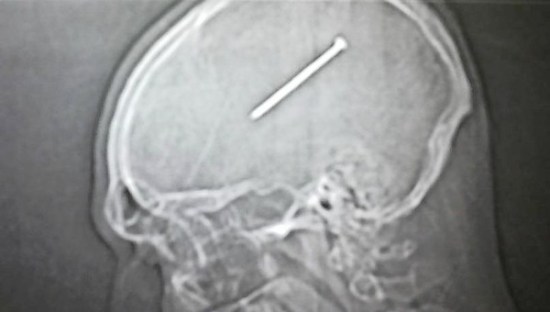

That might be hard to believe given the dramatic X-Ray image pictured above. However, the nail entered the brain high on the back-right side of Autullo’s head. The head of the nail remained lodged in the skull just beneath the skin of his scalp, as if it had been shot into a piece of wood. Because of the direction Autullo is facing in the X-Ray, the nail only appears to be suspended in the middle of Autullo’s head.